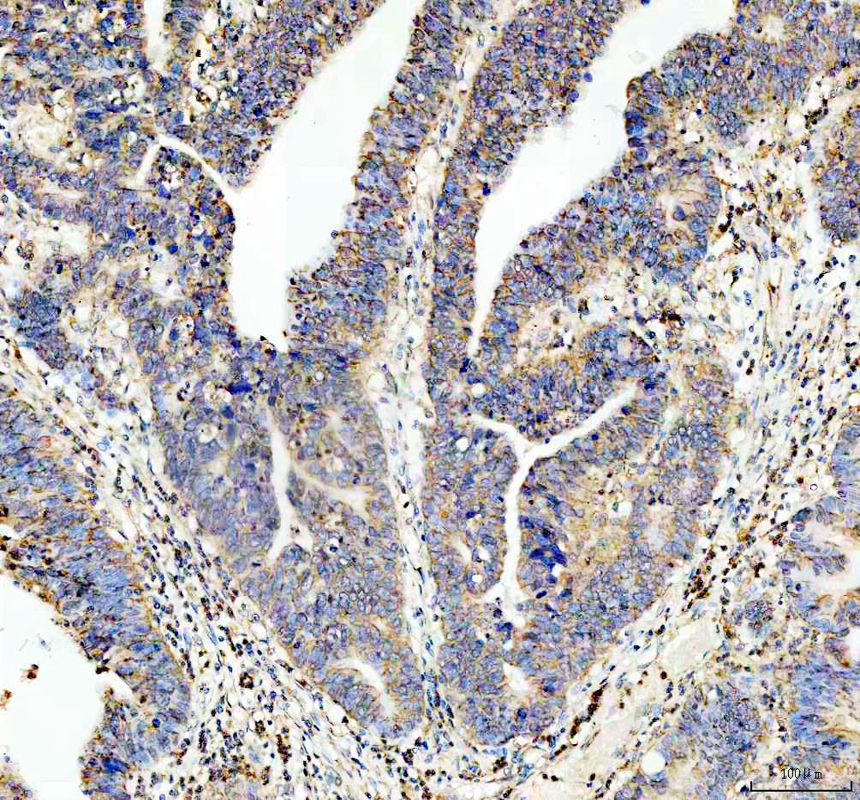

IHC analysis of PSEN1 using anti-PSEN1 antibody (BM5520) .

PSEN1 was detected in a paraffin-embedded section of human stomach cancer tissue. The tissue section was incubated with rabbit anti-PSEN1 Antibody (BM5520) at a dilution of 1:200 and developed using HRP Conjugated Rabbit IgG Super Vision Assay Kit (Catalog # SV0002) with DAB (Catalog # AR1027) as the chromogen.